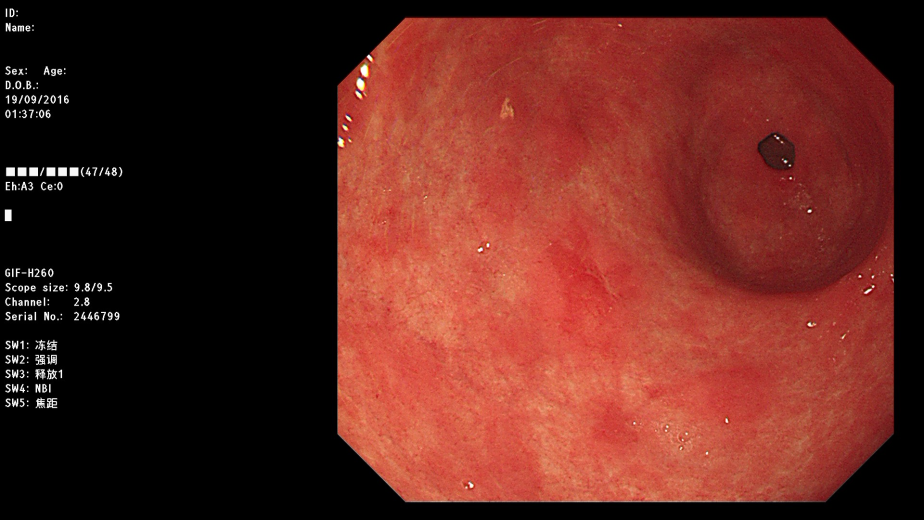

常规的胃镜所见(只是看到粘膜有些发红的斑片)